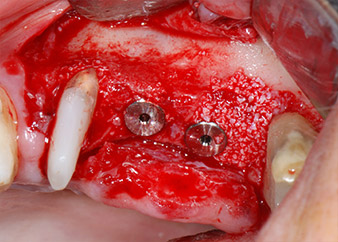

Im folgenden Schritt wurde das jeweilige Implantatbett an den Positionen 25 und 26 mit rotierenden Instrumenten in einem Winkelstück mit einem Übersetzungsverhältnis von 20:1 (WS-75 L G, W&H) und einem vor Kurzem aktualisierten leistungsstarken Implantatmotor präpariert (Implantmed, W&H) (Abb. 8 und 19).

Dann wurden die Implantate (Restore, Keystone Dental) mit dem Implantatmotor eingesetzt (Abb. 11 und 12).